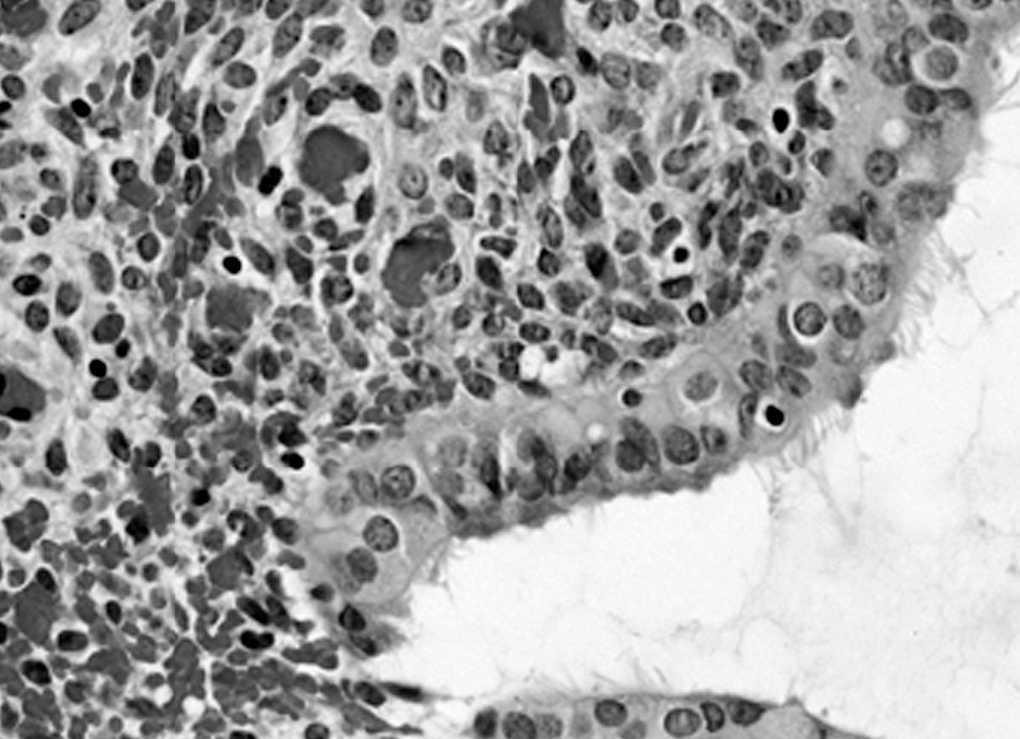

Histológicamente, el nódulo endometriósico se caracteriza por la presencia de los dos componentes del tejido endometrial, las glándulas y la estroma. En el estudio microscópico se observan glándulas revestidas por un epitelio cilíndrico cuya apariencia varía en respuesta a las fluctuaciones hormonales, lo que se traduce en la aparición de fenómenos de hemorragia reciente o antigua en la estroma y en una respuesta inflamatoria secundaria (figs. 1 y 2), aunque hay una escasa correlación entre el aspecto histológico de la endometriosis y el ciclo menstrual7. Se han descrito cambios metaplásicos e hiperplásicos en las glándulas endometriales que excepcionalmente pueden ser asiento de adenocarcinomas8.

Fig. 2. Epitelio glandular (obsérvese la presencia de cilios). Es frecuente la presencia de focos de hemorragia en la estroma (HE x40).